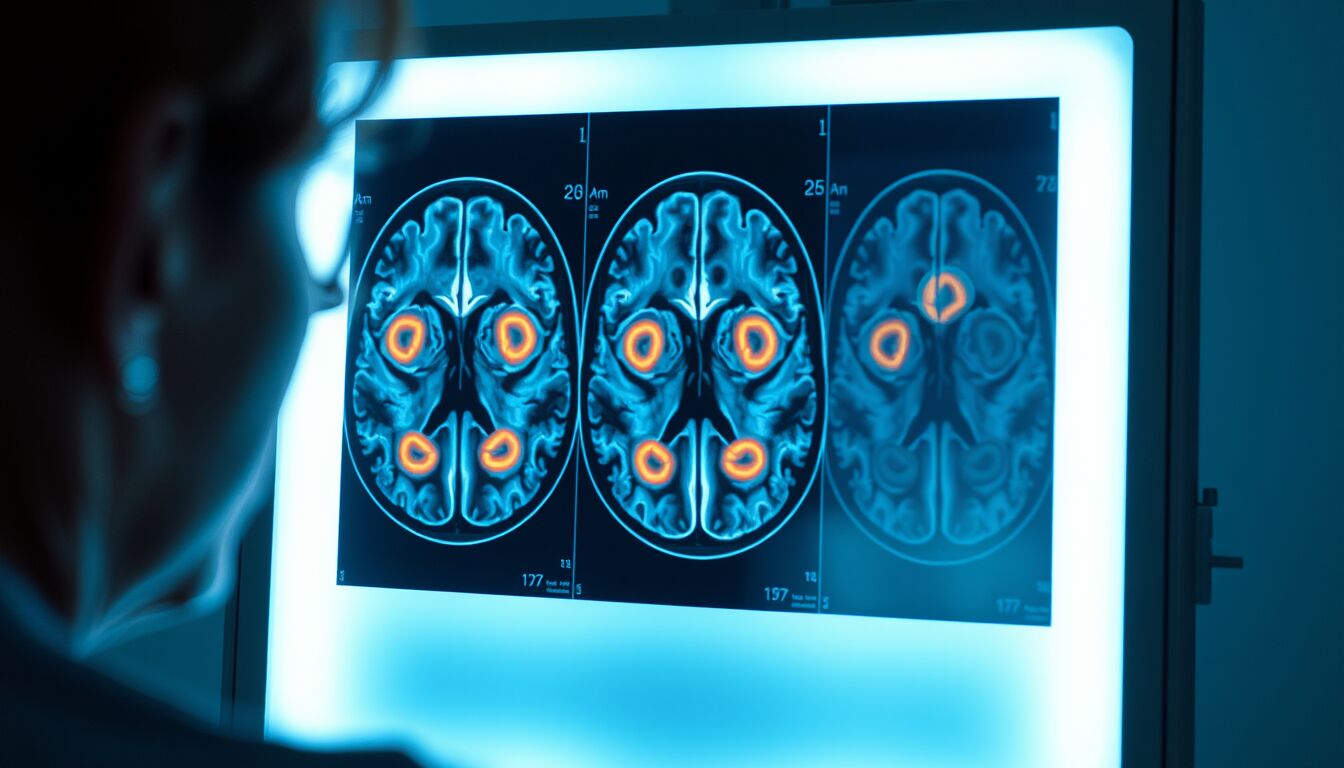

I meningiomi sono tumori in genere benigni che originano dalle meningi, le membrane che avvolgono il cervello. Possono però diventare clinicamente rilevanti comprimendo strutture cerebrali e nervi ottici, con disturbi visivi, cefalea cronica, crisi epilettiche o deficit neurologici.

Nel caso della donna di Crewe, uno dei quattro tumori è stato individuato dietro l’occhio durante esami radiologici di secondo livello. I clinici hanno collegato il quadro alla lunga esposizione a un contraccettivo iniettabile a base di progesterone sintetico, farmaco usato dalla paziente per evitare il ciclo mestruale in modo continuativo.